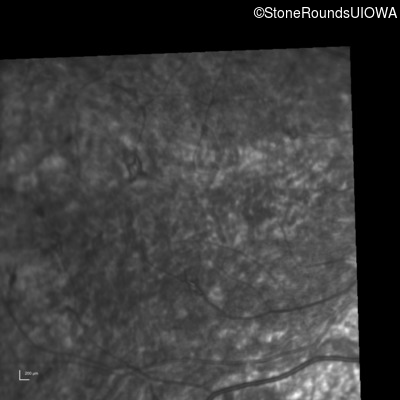

Infrared Fundus Photograph - Right - 5/200 sc

Exemplar